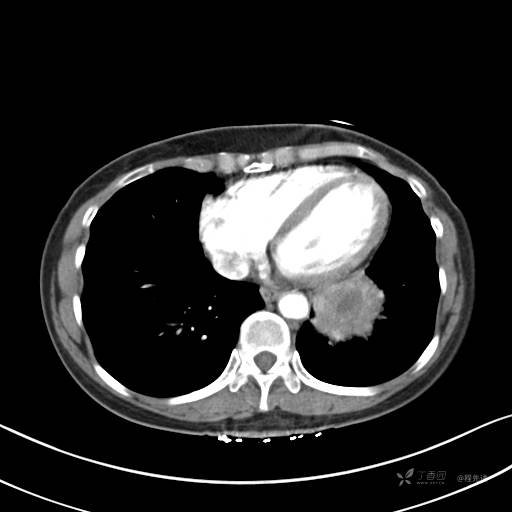

增强静脉期

静脉期CT值约84HU